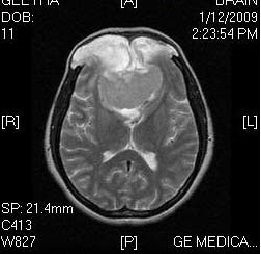

here is an image but i couldn't get a valid code on net the code that i found iy didnt give me back a gray scale image with removed noise but the output of those code is too dark so hope i'll get some help here

so attaching the image here and waiting for response